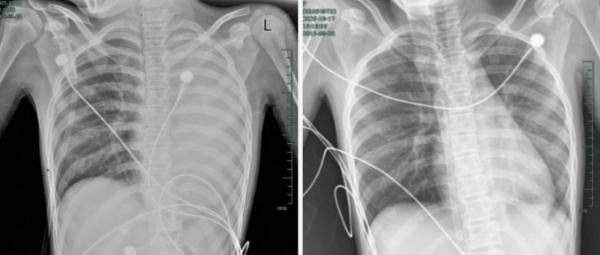

治疗前后影响对比,左肺从“白肺”到正常状态。

什么病?如此来势汹汹?

据介绍,笑笑一开始只是轻微咳嗽,发热到38℃,检查提示肺炎、肺不张,转诊到浙大四院儿科时,病情已经急剧恶化,出现呼吸急促、胸闷胸痛,体温38.5℃,只能靠5L/min的面罩吸氧维持血氧,胸片显示左肺已完全呈 “白肺” 改变,肺部炎症进展迅猛。

儿科虞琳副主任医师判断,笑笑极有可能是患上了“塑型性支气管炎”。